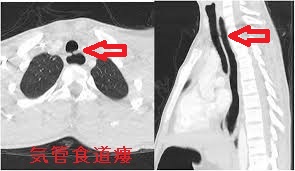

気管食道瘻

気管食道瘻 CT画像